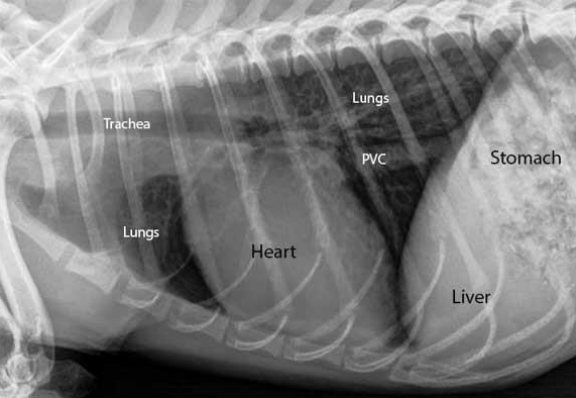

폐의 정상 위치

- 앞쪽으로는 thoracic inlet, 뒤쪽으로는 7th rib, 배쪽으로는 sternum, 등쪽으로는 11th ICS까지 확장되어 있음.

Radiography

- 방사선은 최대 흡기 기준 (maximal inspiration)

- 호흡이 너무 안 좋으면 그냥 DV로 엎드려 찍기도 한다

🔷 Thoracic radiography 해석하기

검은색 배경 : 폐포 (공기를 머금어서)

거미줄처럼 이어진 것 : interstitium (간질)

V : 혈관

검은 줄 : 기관지